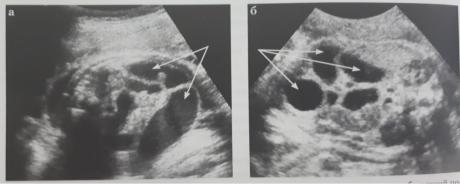

УЗД плода – атрезия тонкого и толстого кишечника - на 20-24-29 нед. – делятация (расширение) петель кишечника на разных уровнях (множество расширенных петель кишечника) с усиленной перистальтикой и плавающими частицами мекония, количество петель отражает уровень непроходимости.